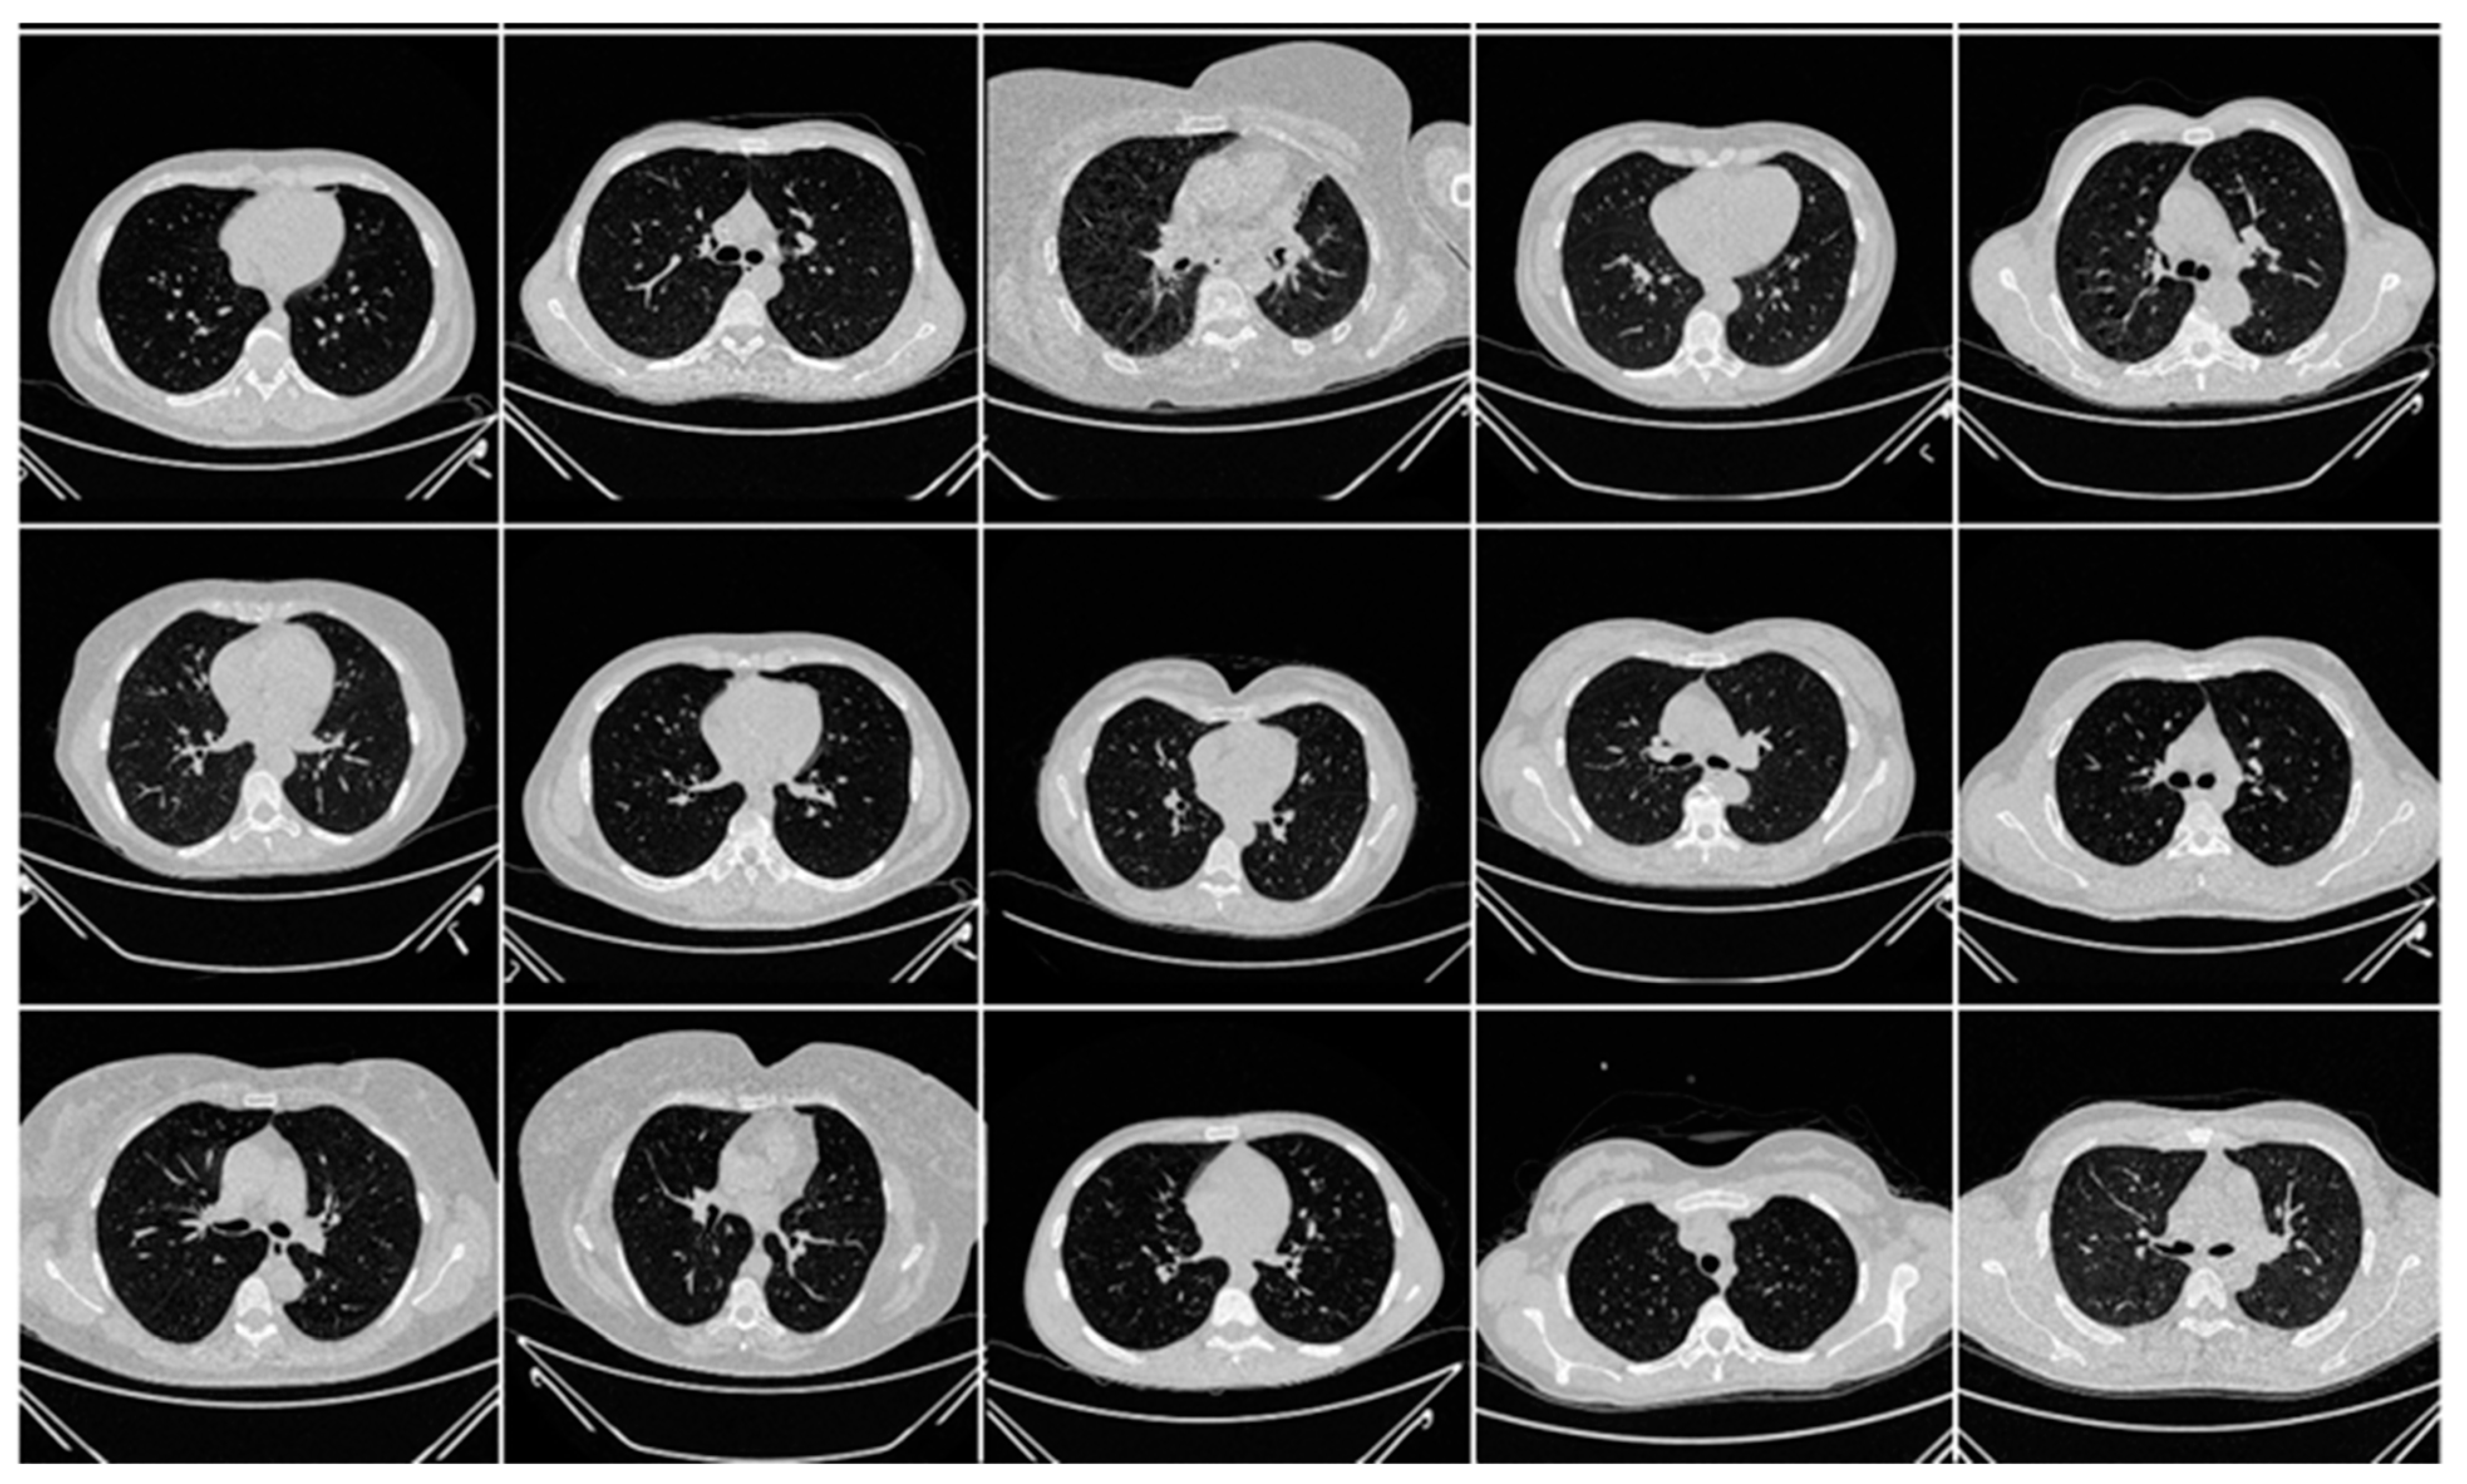

The second data set included 72 NovMED COVID-19-positive individuals. Figure 2 included 47 males, and the remainder were female. An RT-PCR test was conducted to confirm the presence of COVID-19 in the selected cohort, with an average value of approximately 2.4 GGO, consolidation, and other opacities. Of the 72 NovMED patients, 61% had a cough, 9% had a sore throat, 54% had dyspnea, 42% had hypertension, 12% were diabetic, 11% had COPD, and 11% were smokers. In total, 10 patients died due to COVID-19 infection in this cohort. Figure 3 shows NovMED(control) datasets from Italy. The COVID (Croatia) dataset had dimensions of 512 × 512 and 5396 raw images, COVID (ITA) had dimensions of 768 × 768 and 5797 raw images, and control (Italy) had dimensions of 768 × 768 and 1855 raw images.

Figure 3.

Raw “Control CT slices” images taken from NovMED dataset.

Figure A3.

Raw “COVID-19 CT slices” taken from NovMED dataset.